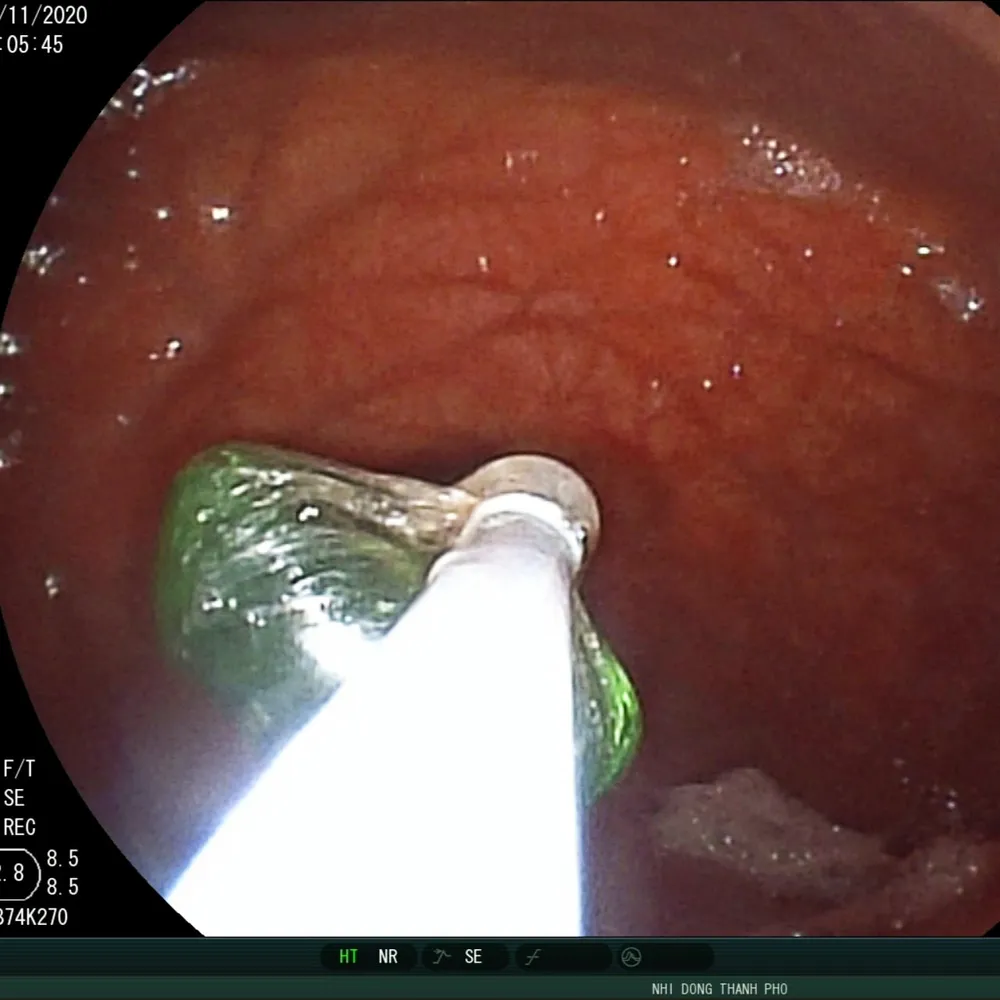

Viên sỏi thủy tinh trong thực quản bé trai 3 tuổi được các bác sĩ gắp kịp thời

Kết quả chụp X-quang ngực thẳng nghiêng phát hiện dị vật tròn 1,5 x 1,5 cm mắc tại 1/3 trên thực quản của bé.

Các bác sĩ sử dụng kỹ thuật lấy dị vật theo đường tiêu hóa lấy ra được một viên sỏi kích thước 15x15 mm, hình ê-líp không góc cạnh.

Tại Bệnh viện Nhi đồng Thành phố, các bác sĩ tiến hành siêu âm bụng, kết quả không ghi nhận bất thường, mời hội chẩn tai mũi họng, tiêu hóa và được ekip nội soi tiêu hóa do bác sĩ Lê Đức Lộc gắp ra kịp thời sau đó.